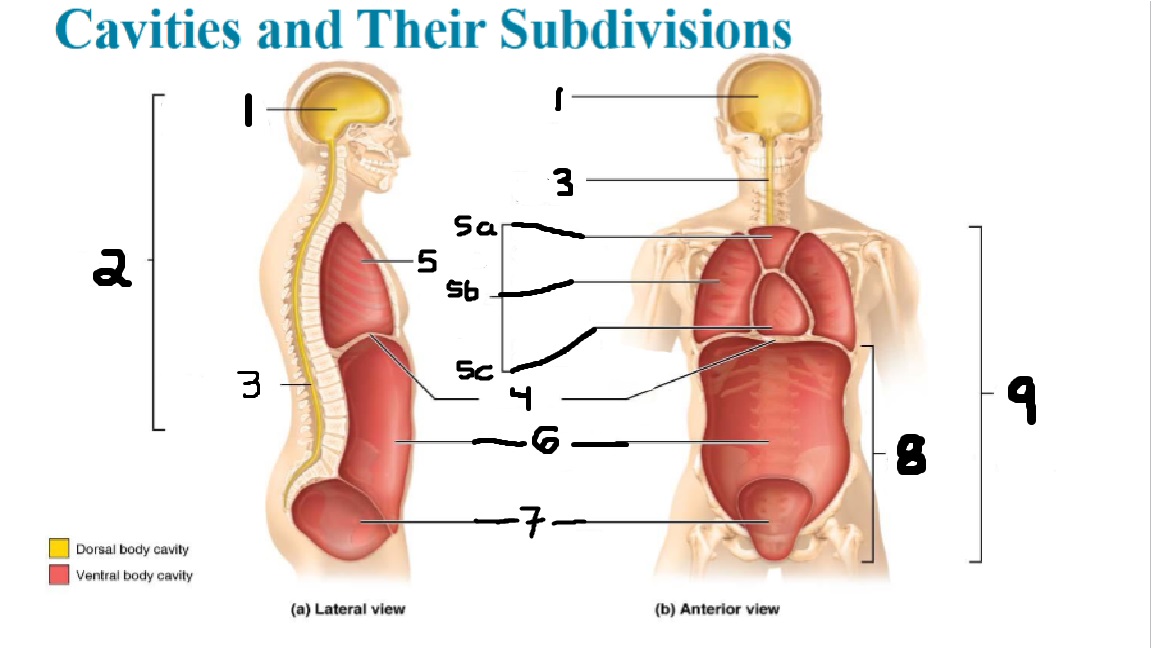

What cavities are part of the dorsal cavity?

The cranial and the Spinal (vertebral) cavities

What kind of cavity is labeled 2?

The dorsal body cavity (containing the cranial and spinal cavities)

What is the purpose of the dorsal cavity?

protects the nervous system

What is the main organ encased by the cranial cavity?

the brain

What cavity is labeled #1?

The cranial cavity

What is the main organ encased by the vertebral cavity?

the spinal cord

What is another word for the vertebral cavity?

the spinal cavity, or the spinal canal

What body cavity is labeled 3?

the vertebral cavity.

What cavities are included in the ventral cavity?

the thoracic, abdominal, and pelvic cavities.

What body cavity is labeled #6?

the abdominal cavity.

What are the main organs of the abdominal cavity?

the digestive organs such as the stomach, intestines, spleen and liver

What cavities are included in the Abdominopelvic cavity?

the abdominal cavity and the pelvic cavity

What body cavity is labeled #8?

The Abdominopelvic cavity

What does the diaphragm separate?

the thoracic and the abdominal cavities

What is labeled #4?

the diaphragm

What organs does the pelvic body cavity contain?

urinary/reproductive organs and rectum

What is labeled #7?

the pelvic cavity

What does the thoracic cavity encase?

the heart and the lungs

What is labeled #5?

the thoracic cavity

What part of the thoracic body cavity is labeled 5a?

superior mediastinum

What part of the thoracic body cavity is labeled 5b?

pleural cavity

What part of the thoracic body cavity is labeled 5c?

pericardial cavity within the mediastinum

What body cavity encloses the heart?

the pericardial cavity.